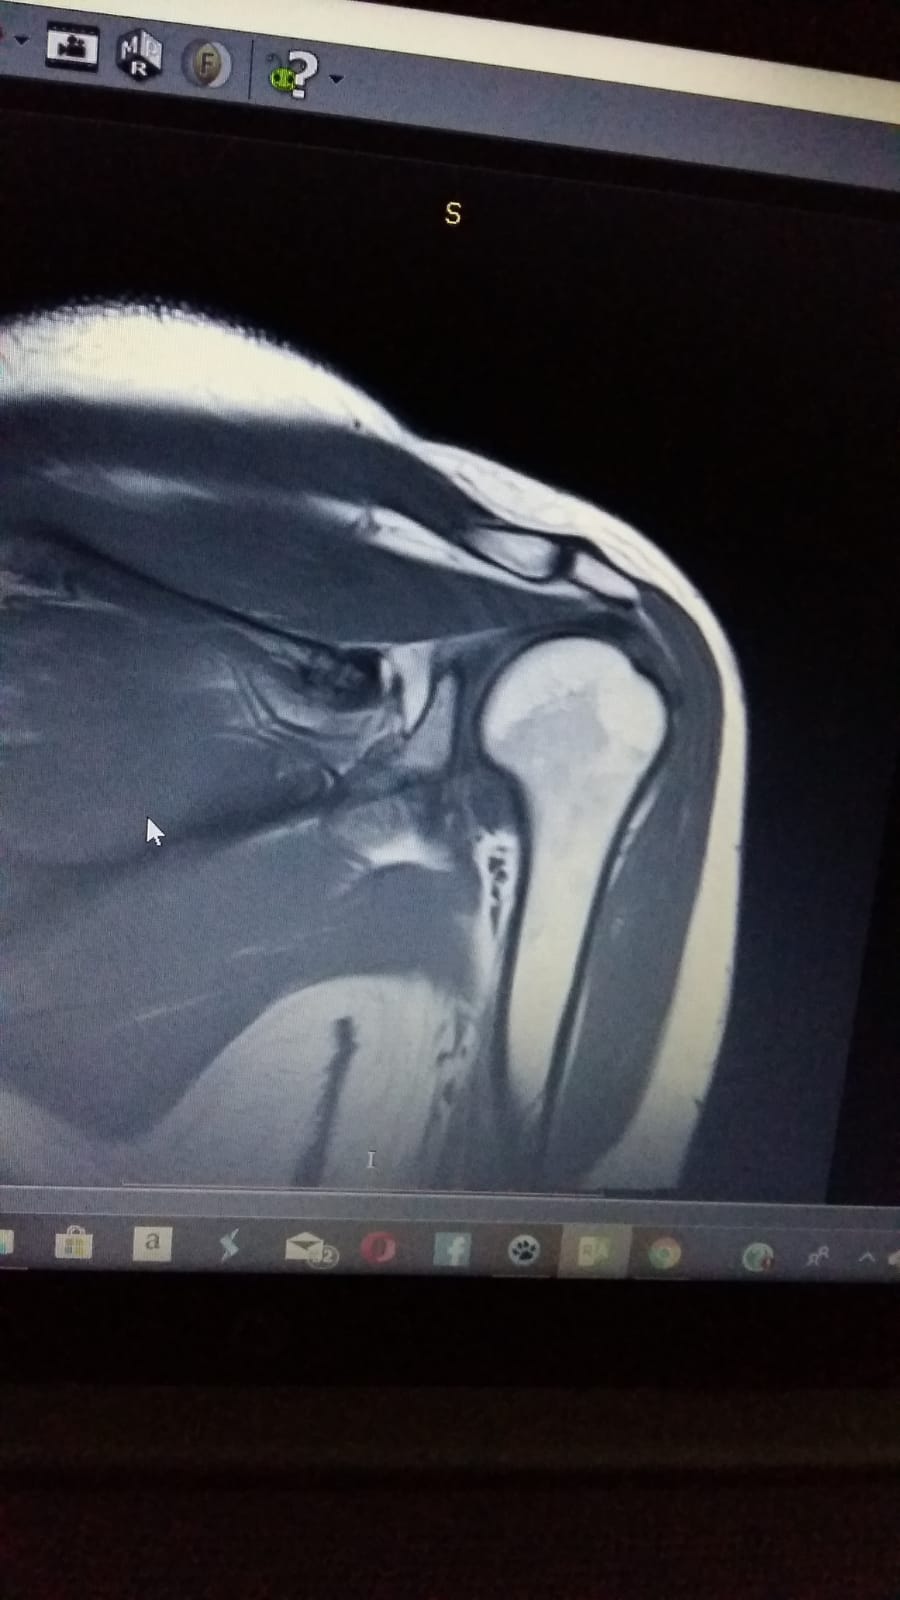

Schulterprobleme?

MRT Schulter links weiße FleckenWenn Ihr Schmerzen in der Schulter habt, solltet Ihr auf jeden Fall einen Arzt aufsuchen. Aber wisst Ihr auch, dass manchmal eine MRT-Aufnahme notwendig ist, um die Ursache der Probleme zu finden?

Auf dem Bild seht Ihr eine MRT-Aufnahme einer Schulter mit weißen Flecken. Diese können auf verschiedene Erkrankungen hindeuten, z.B. eine Entzündung oder Verletzung.